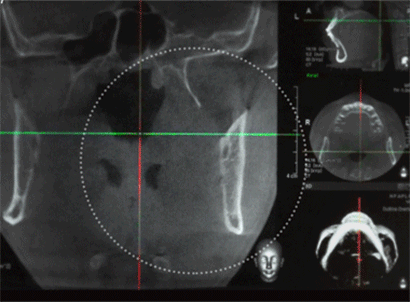

Алдааг урьдчилан тооцоолох боломжтой нүүрний ясны шинжлэх ухаан

Дэвшилтэд технологийг ашиглаж эрүүнээс тархи хүртэл үргэлжилдэг мэдрэлийн судас Дагасан замыг нарийн оношилж, бага зэргийн алдааг ч урьдчилан тооцоолох боломжтой аюулгүй мэс засал